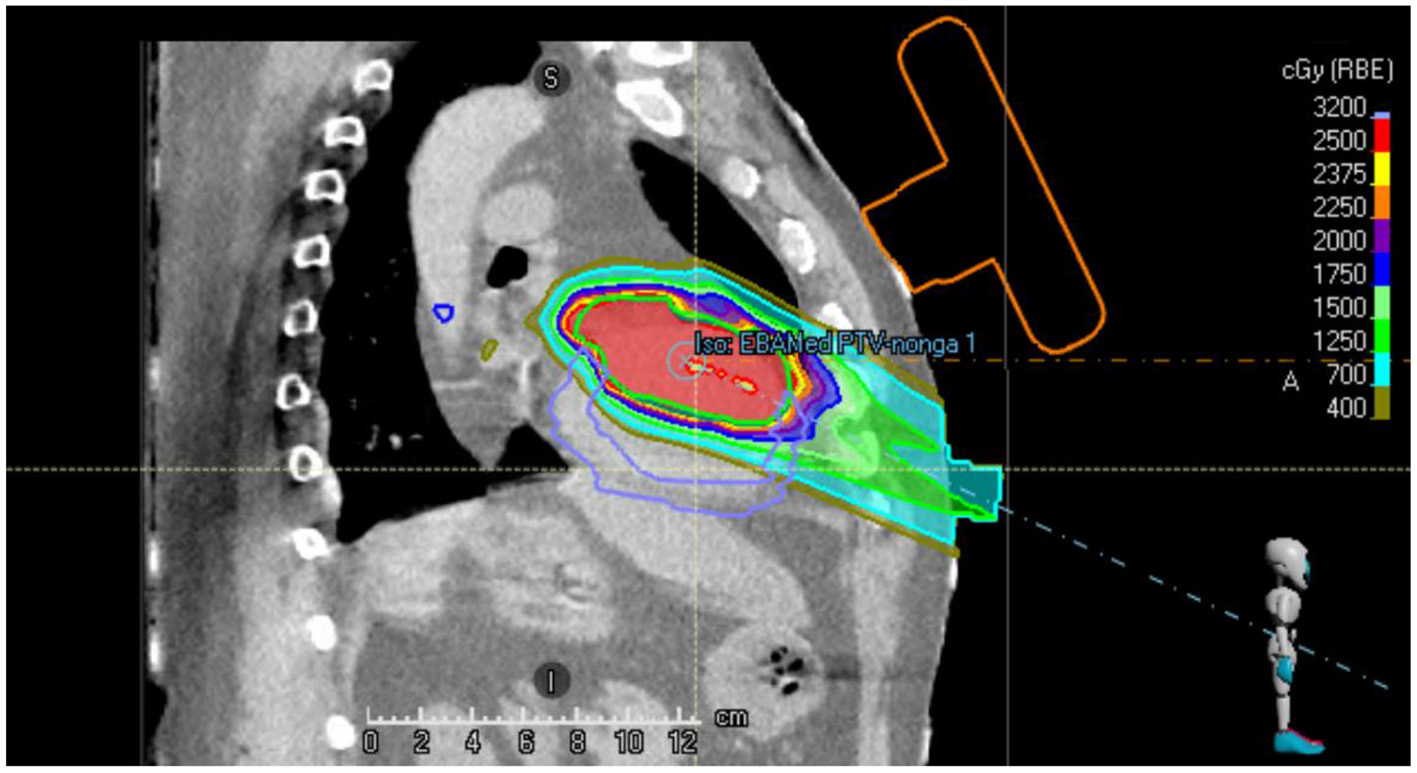

Figure 2 shows a sagittal slice of the proton treatment plan that has been generated for the patient studied in this case report. It can be observed that the beams do not intersect the orange contour of the virtual US probe.

Figure 2

Sagittal slice of the single beam proton plan generated for the VT patient. The location of the virtual US probe with localization marker on the chest of the patient is shown in orange.